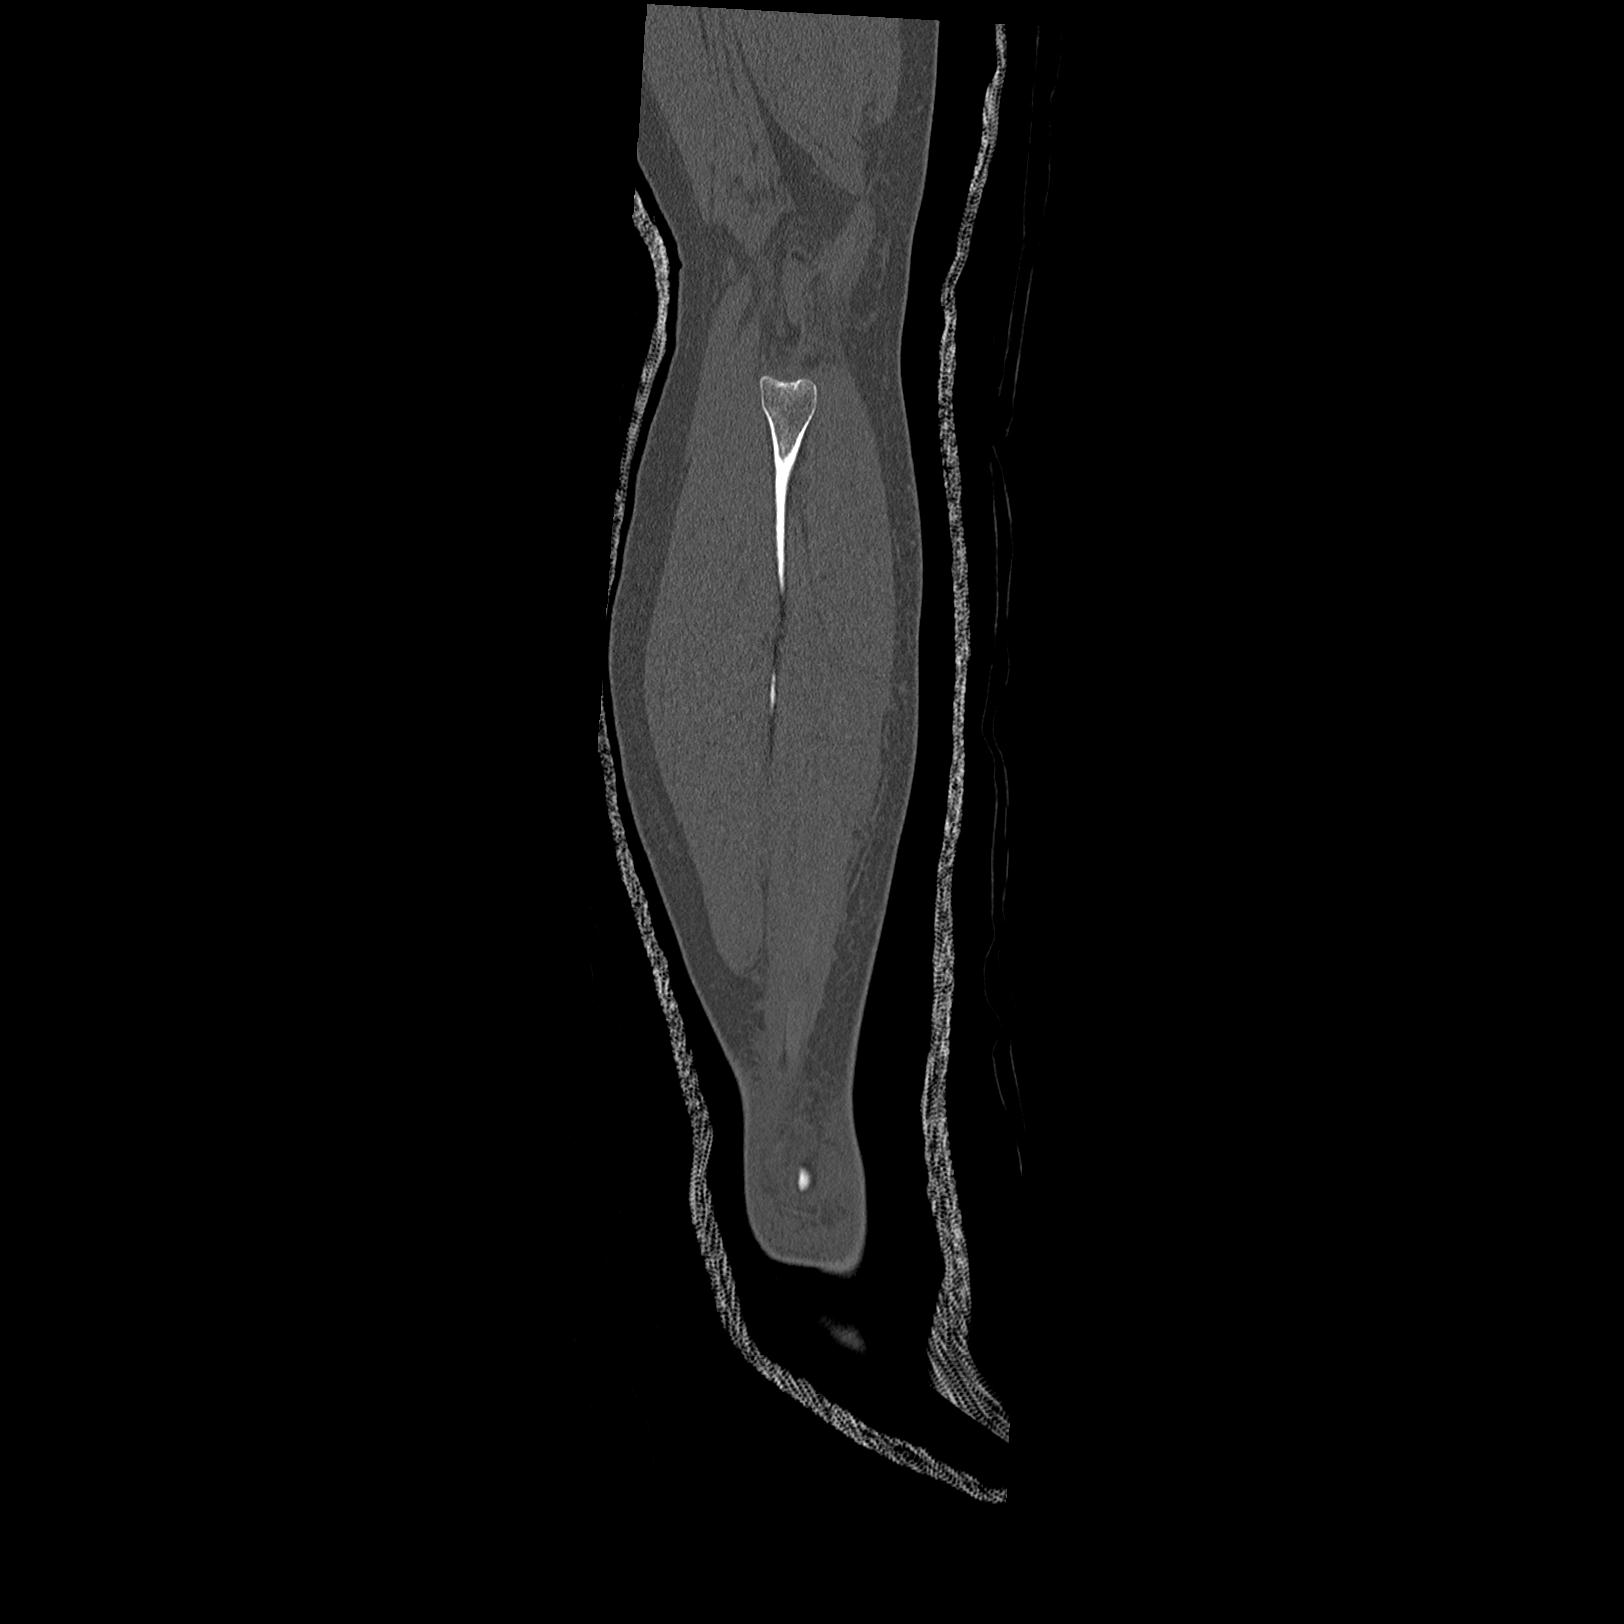

102803 1/12(キウスなし) 1/27 左下腿 4R 30歳女性 左脛骨軸内釘